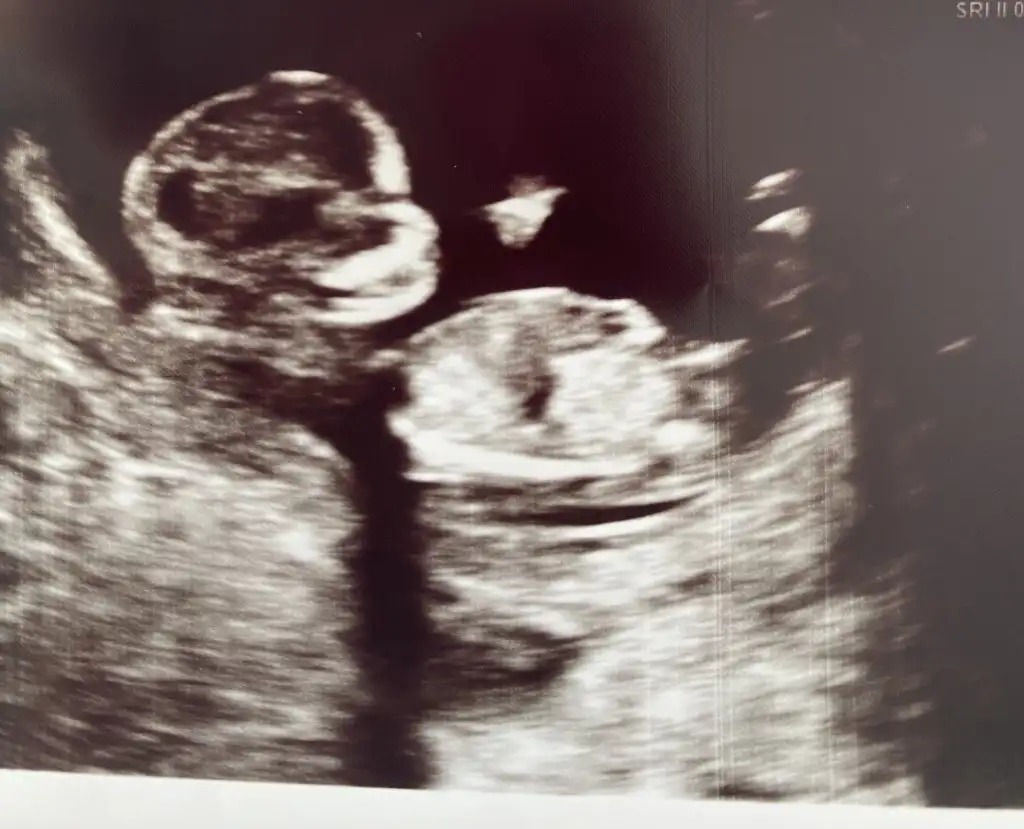

12 hafta acaba sizde fotosu varmi sizinkinin ultrasonunun?

B8F13DF5-5013-4974-89DF-EF0880B51AFA.webp

Burdaki 12-13 sanırım